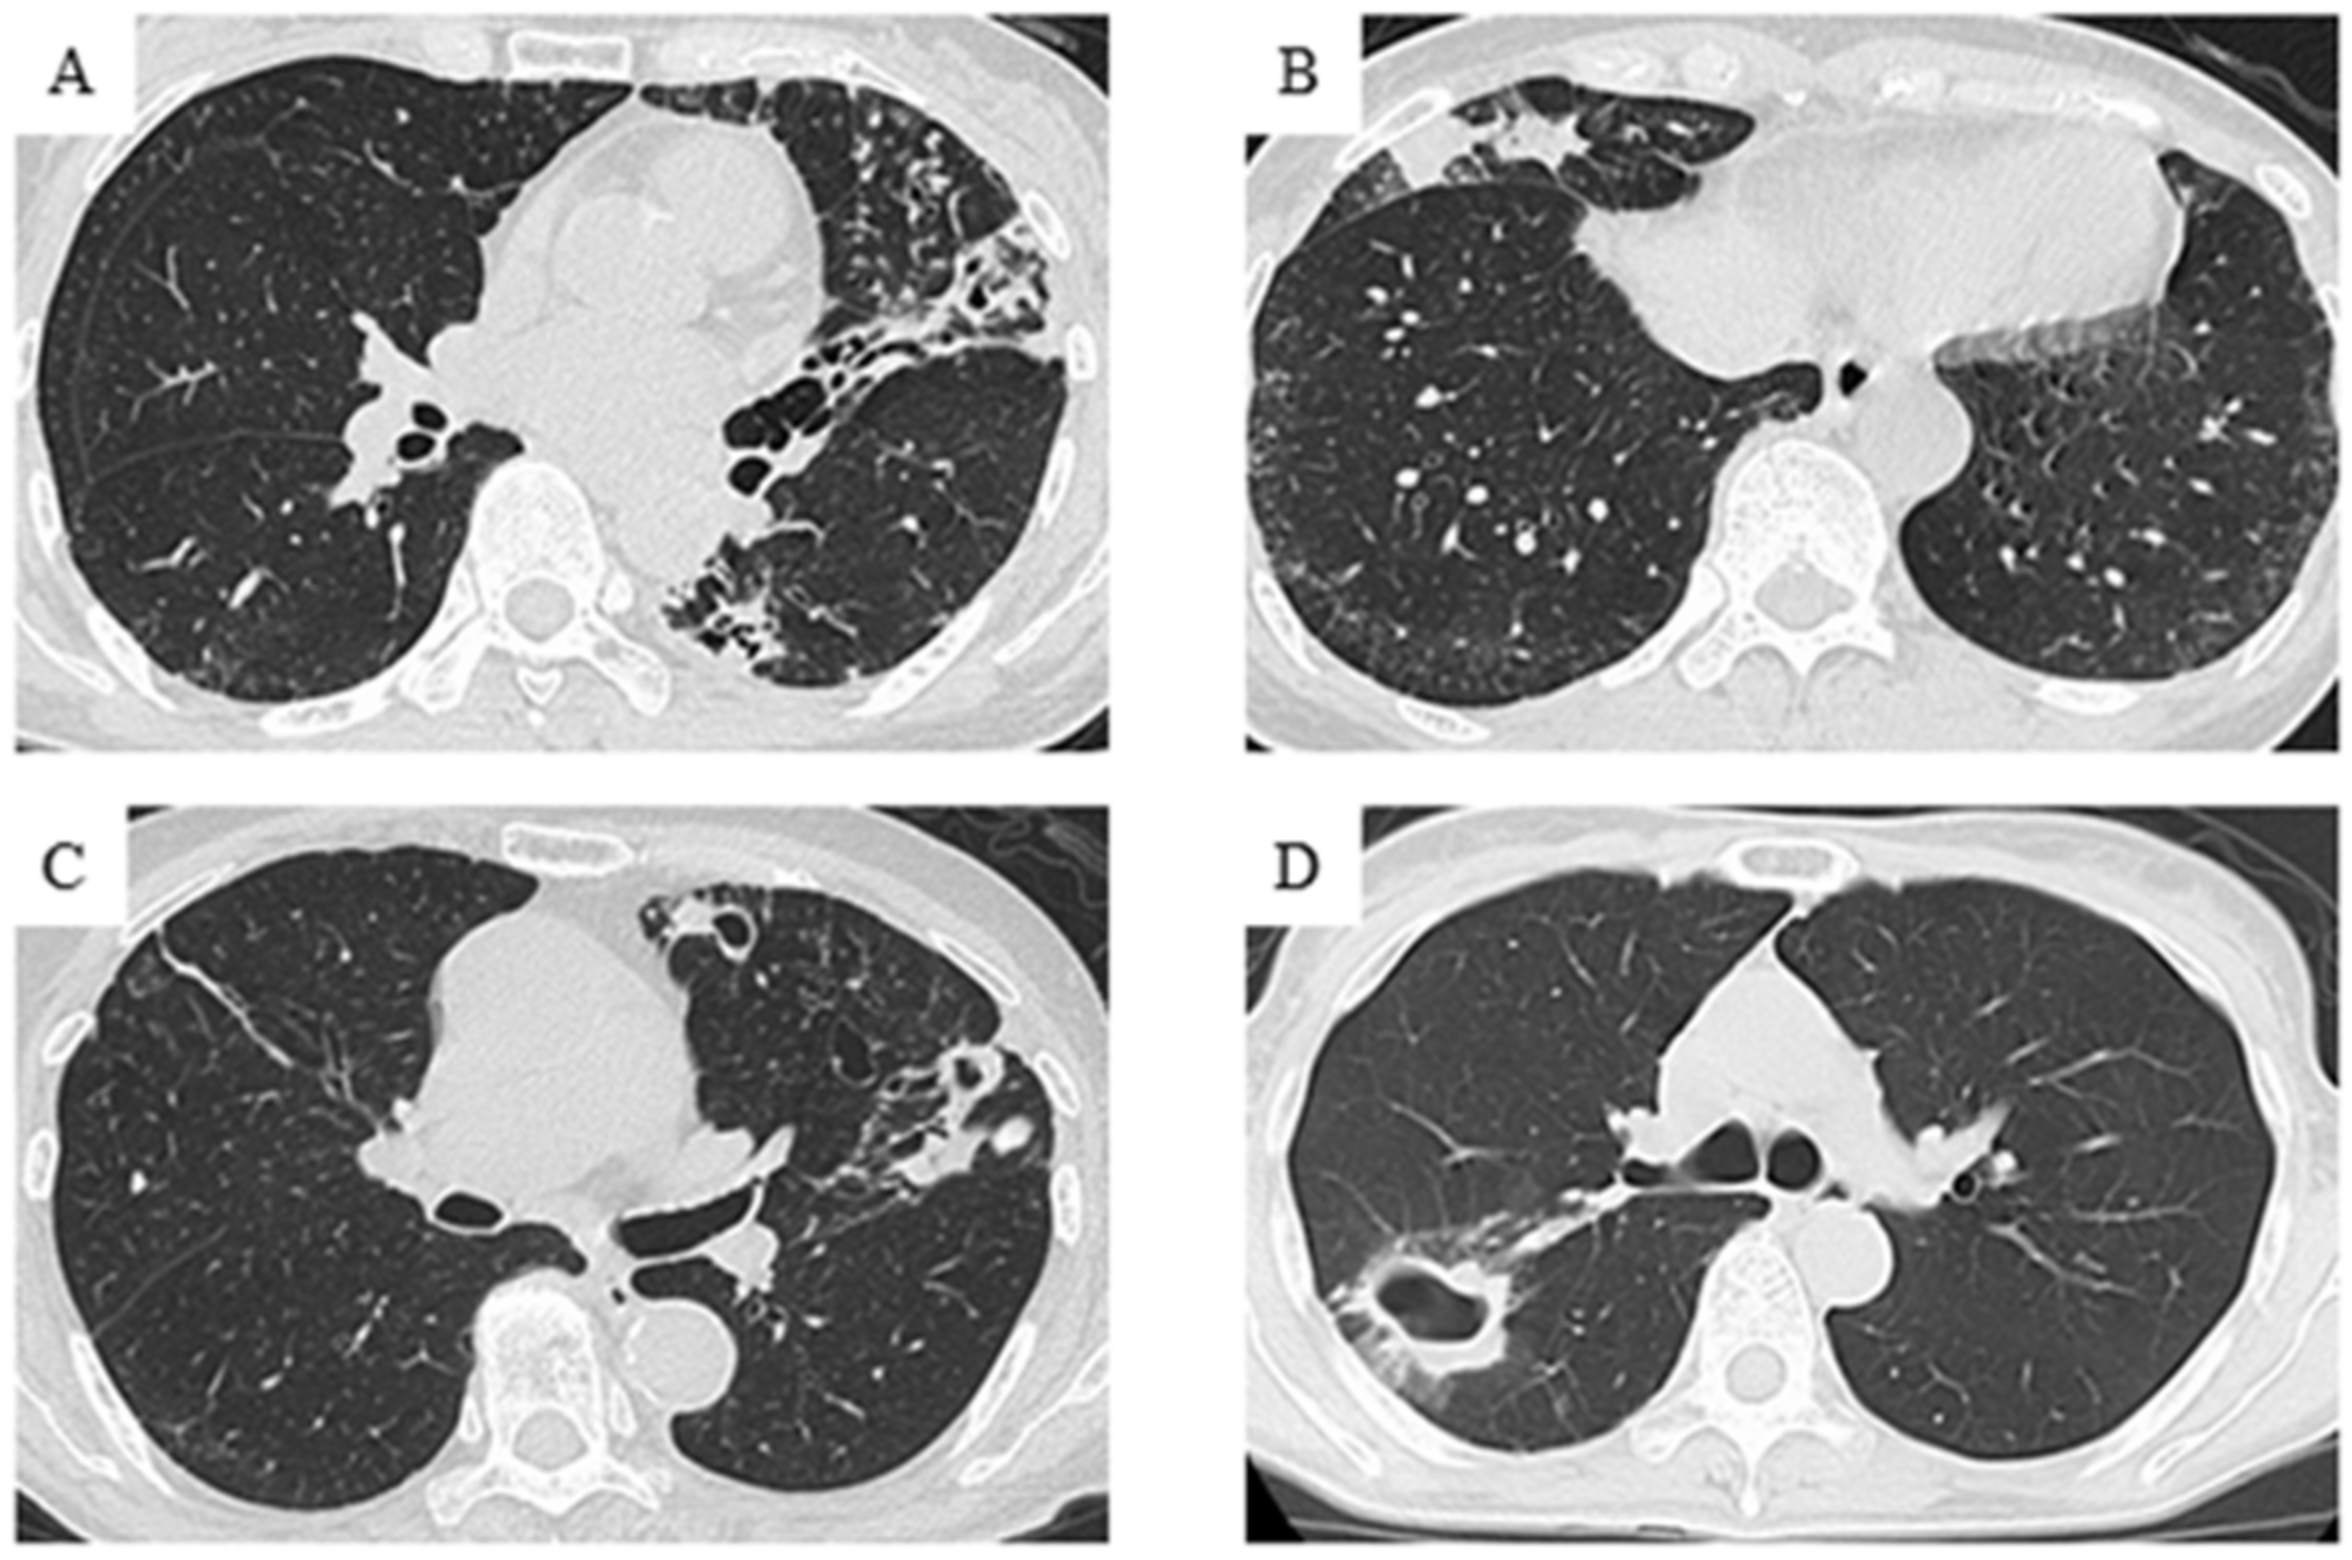

2.4. Radiological Evaluation

| Chest CT findings | ||||

| Non-cavitary NB | 102 (70.8) | 40 (64.5) | 62 (75.6) | 0.15 |

| Cavitary NB | 33 (22.9) | 18 (29.0) | 15 (18.3) | 0.13 |

| FC | 6 (4.2) | 4 (6.5) | 2 (2.4) | 0.23 |

| Unclassified | 3 (2.1) | 0 (0.0) | 3 (3.7) | 0.13 |

| Cavitary NB+FC | 39 (27.1) | 22 (35.5) | 17 (20.7) | <0.05 |

| Non-cavitary NB | 33 (50.0) | 14 (42.4) | 19 (57.6) | 0.22 |

| Cavitary NB | 27 (40.9) | 16 (48.5) | 11 (33.3) | 0.21 |

| FC | 5 (7.6) | 3 (9.1) | 2 (6.1) | 0.64 |

| Unclassified | 1 (1.5) | 0 (0.0) | 1 (3.0) | 0.31 |

| Cavitary NB+FC | 32 (48.5) | 19 (57.6) | 13 (39.4) | 0.14 |